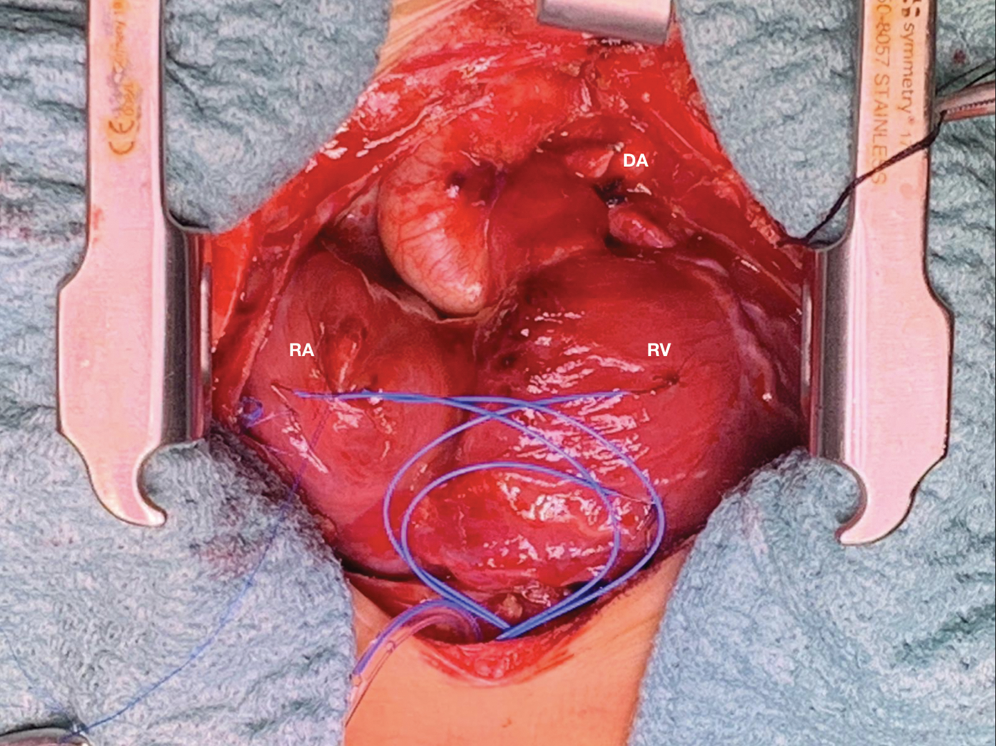

High intravenous dosage of Prostaglandin E1 (PGE1) was administered immediately. Chest X-ray showed severe cardiomegaly and wall to wall heart (Fig. 3A). After diuretic and dopamine therapy, TR improved from severe to trivial, but persisted functional PA with a thickened non-opening pulmonary valve without anterograde flow. Multidisciplinary team decision was to progressively reduce Prostaglandin’s dose and clinical observation. Clinical conditions progressively worsened with an imposing right heart failure characterized by ascites, hepatomegaly and anuria (creatinine: 2 mg/dl). Despite diuretic therapy and paracentesis drainage, we faced with further deterioration of clinical conditions such as increase lactates levels (6.5 mmol/l) and lower peripheral oxygen saturation of 75%. Serial echocardiograms documented persistence of a large PDA and limited opening of the pulmonic valve cusps, with initial mild anterograde flow. After 5 days of ineffective Ibuprofen administration, surgical PDA ligation was indicated and performed (Fig. 4). By sternotomy approach the first surgical findings were the evidence of cardiomegaly (Fig. 5) and a very large PDA that was ligated. Immediately after the procedure, progressive reduction of the right chambers’ enlargement and oxygen saturation improvement (up to 95%) was noted. Intraoperatory transesophageal echocardiography showed normal opening of the pulmonary valve and persistence of trivial tricuspid valve regurgitation.

Figure 5: Surgical picture of wall to wall heart after ligation of ductus arteriosus. DA ductus arteriosus, RA right atrium, RV right ventricle